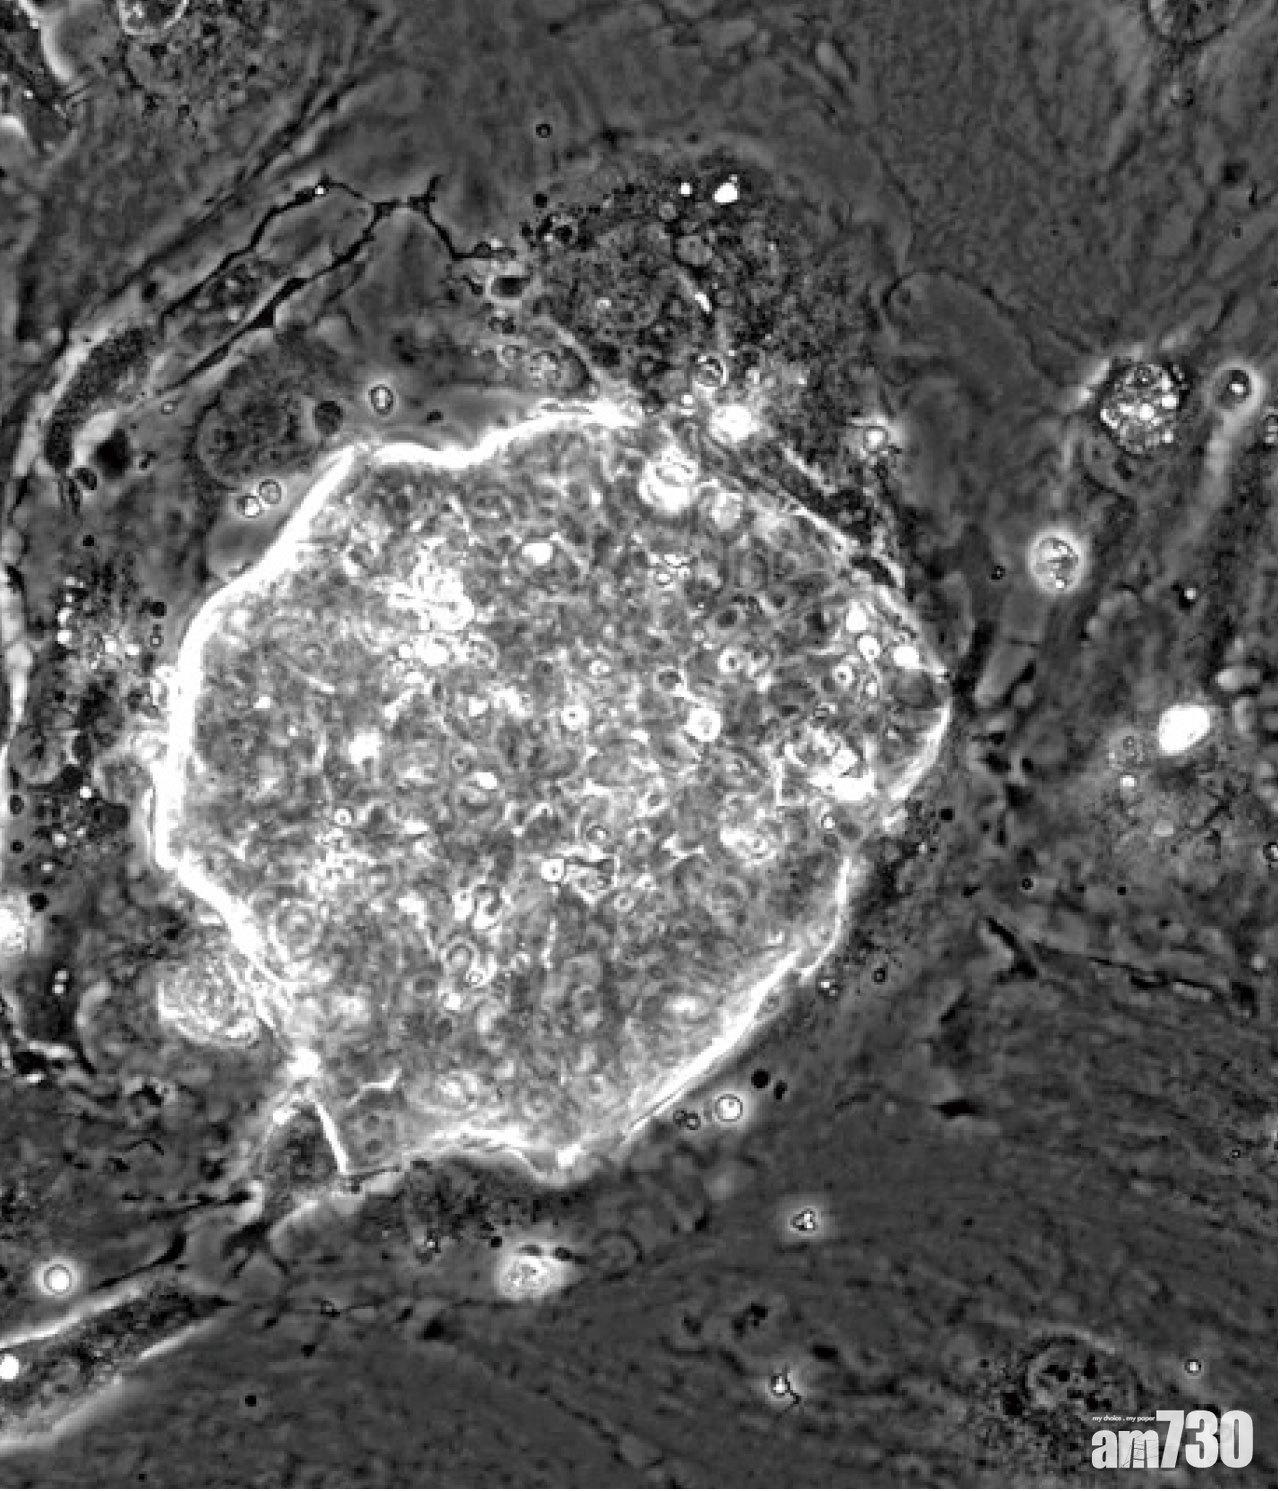

豬胚胎擴展潛能胚胎幹細胞 (pEPSC)

由香港大學李嘉誠醫學院的科研團隊主導,與英國及德國研究人員合作,研究證實除了在人類外,豬也能取得具擴展潛能幹細胞(EPSCs),且首次在豬隻早期胚胎中取得全能性幹細胞,可經克隆技術培養出胚胎及其他身體器官;有別於以往醫學研究從胚胎內抽取的多功能幹細胞,只能培育出胚胎以外的器官。

今次抽取的全能性胚胎幹細胞,需要於哺乳類動物著床前1至4天抽取,以建立幹細胞培養體系,並系統地分析幹細胞的發育、細胞和分子特徵;其自我更新能力更可經基因編輯培育出胚胎,有助研究不育,及懷孕疾病的病因。負責今次研究的劉澎濤教授指,豬具有重大生物醫學研究價值,因其遺傳基因、身體構造及生理機能(如器官大小)與人類相近,有助研究未來器官移植等醫學發展。